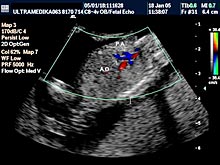

D) Četvrti UZ marker koji mora biti proveren je procena PI (pulzativnog indeksa) tj. procena otpora proticanju krvi kroz venski sud koji dovodi krv u srce ploda i naziva se Duktus venozus! Ova struktura je veličine nekoliko milimetara i pouzdano se može kodirati Braund Band CD i kolor Power Dopplerom. Praktično samo aparati velikih mogućnosti koji koriste ovu tehniku mogu u velikom procentu tj kod većine trudnoća u ovoj gestacionoj starosti registrovati patološki protok u Duktusu venozusu!

Inače patološki protok u ovom malom krvnom sudu je od velikog značaja jer može ukazivati da plod ima hromozomsku anomaliju ili urođenu srčanu manu!